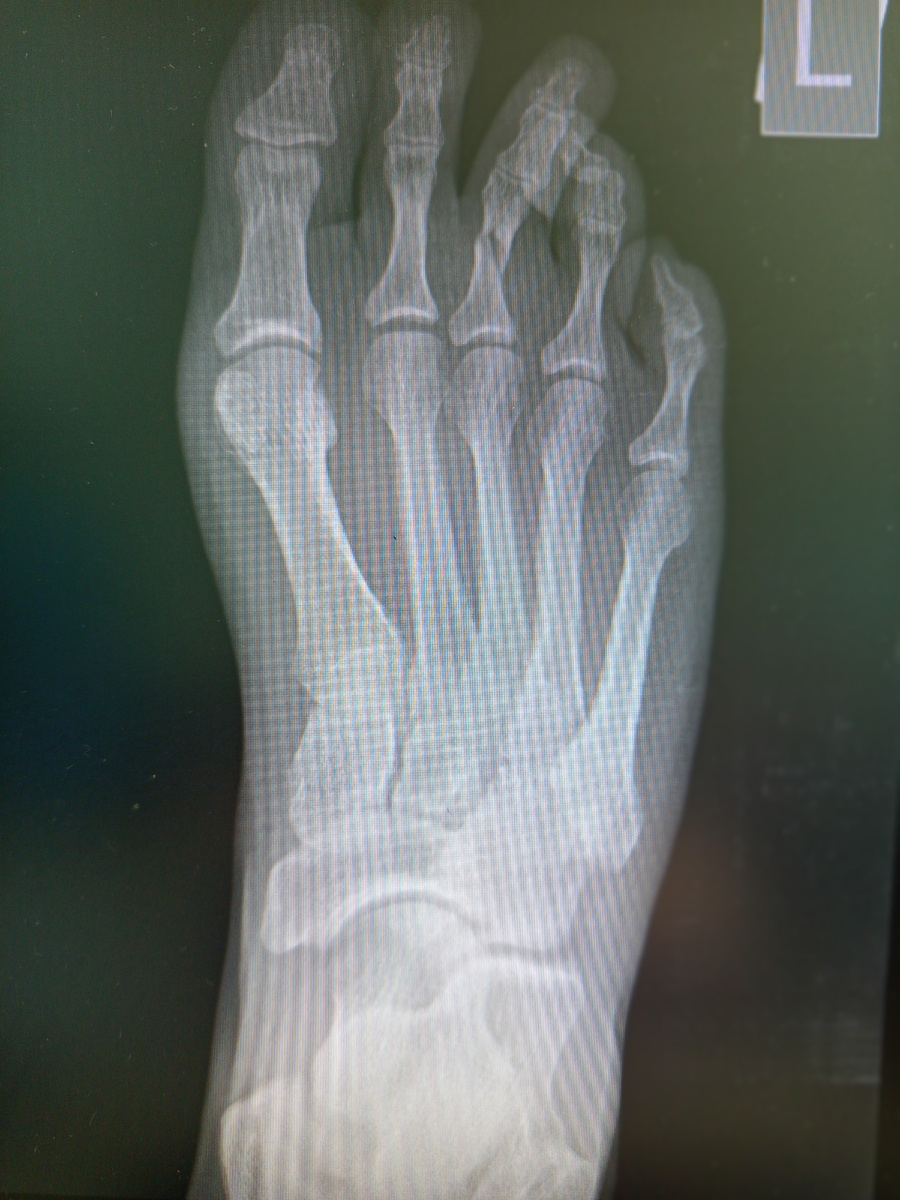

Мужчина пришел , тоже на снимок стопы , сломал пятую плюсневую кость.

–Тоже об диван ударились?

–Почти, об стену.